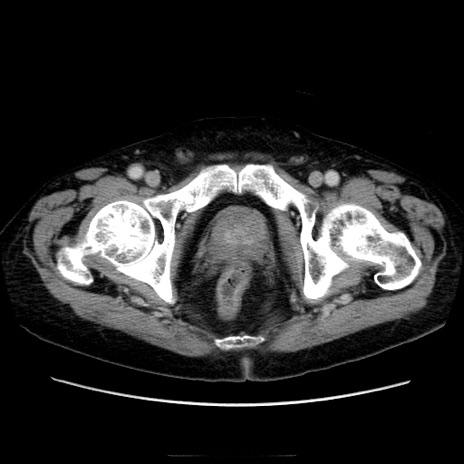

症例21(横断像)

【症例】70歳代男性

【主訴】腹痛

【現病歴】肝硬変・肝細胞癌にてかかりつけの方。約9時間前に食後より腹痛出現。症状が徐々に増悪し、嘔吐出現したため来院。

【既往歴】肝硬変、肝細胞癌(RFA、TACE後)

【身体所見】意識清明、表情苦悶様、BT 36℃、BP 129/78mmHg、P 88bpm、SpO2 97%(RA)、右上腹部から心窩部にかけて圧痛あり、反跳痛なし、筋性防御あり。

【データ】WBC 5800、CRP 0.16